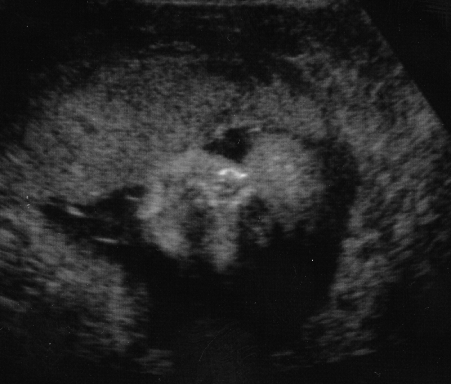

Pregnancy at 10 Weeks

Ultrasound of the baby at 10 weeks

Here the baby is approximately 3.2 cm's